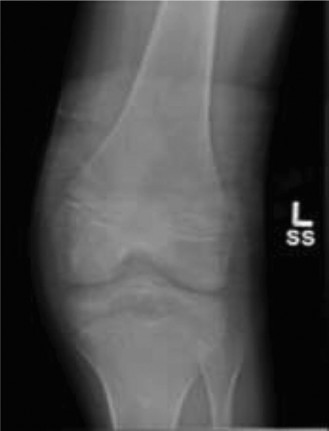

A 27-year-old male patient presents to your office for a second opinion. He has been seen for left knee pain.…